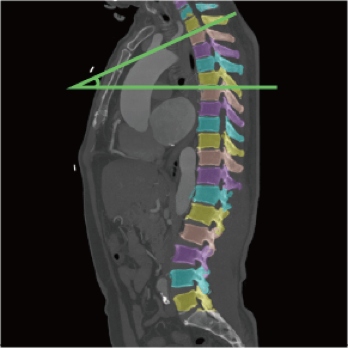

High-power generator delivers high mA output for rapid scanning of complex anatomy and large coverage areas, boosting scan speed while enhancing image signal-to-noise ratio and minimizing artifacts

Wide detector expands single-rotation coverage, shortens exam time, reduces motion artifacts, decreases radiation dose, and saves tube exposure time while effectively lowering operating costs